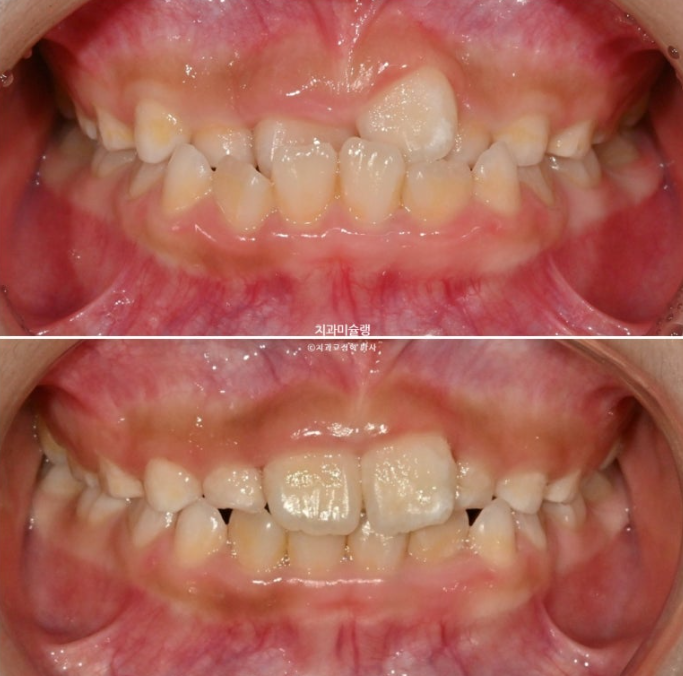

전 후 비교 보겠습니다.

25.04~25.09